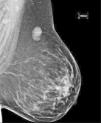

Presentamos el caso de una mujer de 40 años, sin antecedentes de interés, que consulta por palpación de nódulo mamario. La mamografía muestra una lesión nodular, bien delimitada, heterogénea, de 34mm, en el cuadrante superoexterno/prolongación axilar derecha. Se estudia mediante biopsia guiada por ecografía, con resultado de tumor mesenquimal con estroma mixoide, patrón vascular plexiforme y ocasionales células compatibles con lipoblastos. Con este diagnóstico se procede a la exéresis total de la lesión, que a la sección macroscópica muestra nódulo de bordes expansivos, de aspecto gelatinoso y características microscópicas de liposarcoma mixoide. Se presenta el caso y se revisa la literatura médica.

A 40 year old woman presented with a palpable swelling in her right breast. She had no relevant past medical history. Mammography revealed a 34mm, well-defined heterogeneous nodular mass in the axillary tail of the upper external quadrant of the right breast. An ultrasound guided biopsy was performed, in which a mesenchymal tumour was found, with myxoid stroma, a plexiform capillary pattern and scattered cells that resembled lipoblasts. Subsequently, the tumour was excised. Macroscopy showed regular margins on the cut surface and a myxoid lesion. Microscopically the lesion was diagnosed as myxoid liposarcoma. The clinico-pathological features of the case are described and the pertinent literature discussed.